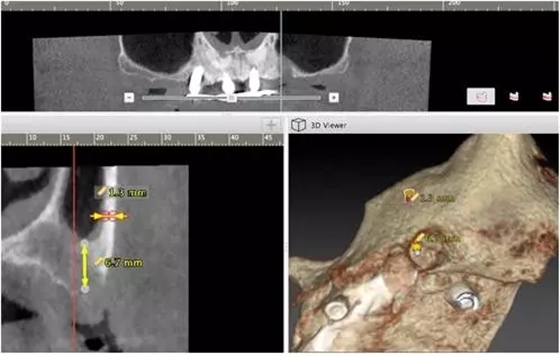

10個(gè)月后出現(xiàn)左上頜咬合痛,X線檢查發(fā)現(xiàn)上頜左側(cè)前磨牙區(qū)傾斜種植體周圍低密度影,臨床檢查種植體松動(dòng),其余種植體骨結(jié)合良好,遂拔除該種植體(圖3-4)。愈合3個(gè)月,CBCT片顯示:25區(qū)種植窩空虛(圖5),愈合不佳,26區(qū)竇底剩余骨高度不足2mm(圖6),其余種植體骨愈合良好,15區(qū)傾斜種植體邊緣骨疑似吸收至第三螺紋(結(jié)合全景片)?;颊咭蠊潭ㄐ迯?fù)。

2、增加上頜種植體數(shù)量,分別與16、25、26植入3顆,行6顆種植體支撐的常規(guī)種植固定義齒修復(fù)(圖7)。16、25、26區(qū)剩余骨高度嚴(yán)重不足是該方案的不利方面,存在因需要上頜竇底提升手術(shù)所帶來(lái)的相應(yīng)手術(shù)風(fēng)險(xiǎn)。但是,上頜竇底提升術(shù)是一個(gè)成熟、可靠的技術(shù)方法,經(jīng)過(guò)與患者充分溝通,最終選擇了這一方案。

1、開(kāi)窗法雙側(cè)上頜竇底提升術(shù),聯(lián)合25區(qū)植骨術(shù);

2、6個(gè)月后延期種植,分別與16、25、26植入3顆種植體(如圖7所示);

上頜竇底提升同期種植的標(biāo)準(zhǔn)是植入種植體能夠獲得初期穩(wěn)定性,竇底植骨材料不具有增加種植體穩(wěn)定性的作用,共識(shí)性意見(jiàn)認(rèn)為剩余骨高度一般應(yīng)大于4-5mm。開(kāi)窗法是骨高度嚴(yán)重不足進(jìn)行上頜竇底提升的有效和可靠術(shù)式。當(dāng)然,國(guó)際上也有關(guān)于采用沖壓法提升剩余骨高度僅有1-2mm上頜竇底的成功病例報(bào)道,但是目前尚缺乏大樣本、多中心重復(fù)性的臨床研究證明,還沒(méi)有得到廣泛的國(guó)際共識(shí),不易作為常規(guī)術(shù)式,有待未來(lái)進(jìn)一步的研究。